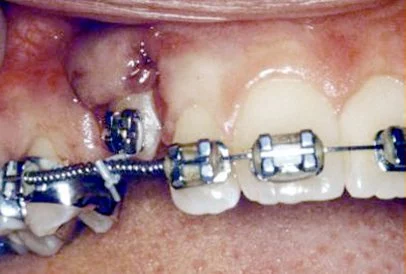

Shortly after surgery (1-14 days) the patient will return to the orthodontist. A rubber band will be attached to the chain to put a light eruptive pulling force on the impacted tooth. This will begin the process of moving the tooth into its proper place in the dental arch. This is a carefully controlled, slow process that may take up to a full year to complete. Remember, the goal is to erupt the impacted tooth and not to extract it. Once the tooth has moved into the arch in its final position, the gum around it will be evaluated to make sure it is sufficiently strong and healthy to last for a lifetime of chewing and tooth brushing. In some circumstances, especially those where the tooth had to be moved a long distance, there may be some minor “gum surgery” required to add bulk to the gum tissue over the relocated tooth so that it remains healthy during normal function. Your dentist or orthodontist will explain this procedure to you if it applies to your specific situation.

These basic principals can be adapted to apply to any impacted tooth in the mouth. It is not that uncommon for both of the maxillary cuspids to be impacted. In these cases, the space in the dental arch will be prepared on both sides at once. When the orthodontist is ready, the surgeon will expose and bracket both teeth in the same visit so that the patient only has to heal from one surgery. Because the anterior teeth (incisors and cuspids) and the bicuspid teeth are small and have single roots they are easier to erupt if they get impacted than the posterior molar teeth. The molar teeth are much bigger teeth and have multiple roots making them more difficult to move. The orthodontic maneuvers needed to manipulate an impacted molar tooth can be more complicated because of their location in the back of the dental arch.